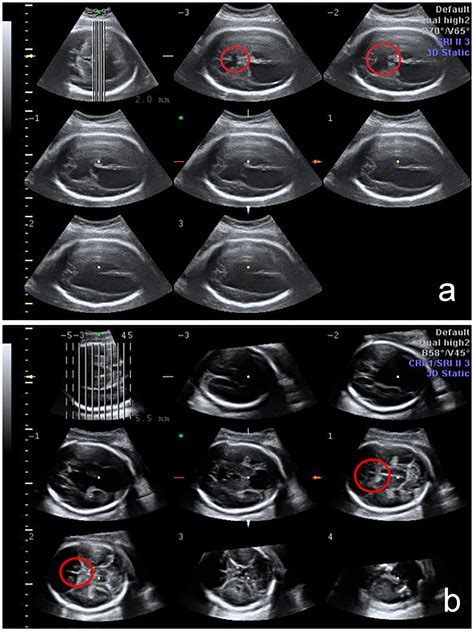

The Cavum Septi Pellucidi is a small, fluid-filled space located between the two leaflets of the septum pellucidum. The septum pellucidum is a thin, triangular, double membrane that separates the lateral ventricles of the brain. During normal fetal development, these two layers are separated by a space, which is the CSP.

The prevalence of a persistent CSP in the adult population is estimated to be between 1% and 3%, though some studies suggest it may be higher in certain demographics. Its appearance on imaging is distinct, typically appearing as a midline, fluid-filled structure that sits between the frontal horns of the lateral ventricles. Radiologists are well-trained to identify this feature and distinguish it from other, more concerning brain cysts or lesions.